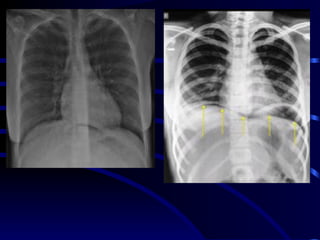

• 4.

cc At the bedside,chest radiography remains the reference for lung imaging in critically ill patients. However, radiographical images are often of limited quality • Movements of the chest wall • Film cassette posterior to the thorax • X-ray beam originating anteriorly, at a shorter distance than recommended and not tangential to the diaphragmatic cupola . Mistaken assessment of : cc • Pleural effusion • Alveolar consolidation • Alveolar-interstitial syndrome Bedside Chest Radiography in the Critically ill

• 5.

(posterioranterior) position. Note that thex-ray tube is 72 inches away. the supine AP (anteriorposterior) position the x-ray tube is 40 inches from the patient.